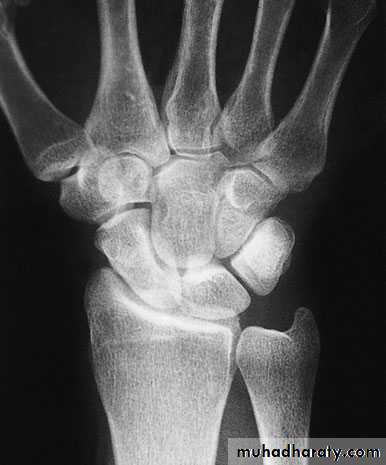

X-ray

Anteroposterior, lateral and oblique views are all essential; often a recent fracture shows only in the oblique view. Usually the fracture line is transverse,and through the narrowest part of the bone (waist), but it may be more proximally situated (proximal pole fracture). Sometimes only the tubercle of the scaphoid is fractured.Treatment

Scaphoid frcature